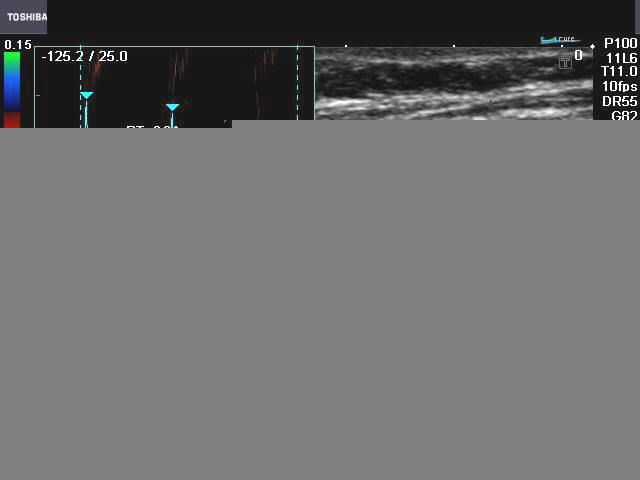

Popliteal vein thrombosis

These color Doppler ultrasound images show the left popliteal vein in an elderly female patient with marked varicose veins of both lower limbs. The most striking finding in this case, is the echogenic oval area partially obstructing flow of blood in the left popliteal vein. This color Doppler finding is typical of thrombus in the popliteal vein. Transverse section color Doppler images show failure to fully compress the affected part of the left popliteal vein, which confirms the presence of a thrombus. Note the flow of blood around the popliteal vein. (POPL Art= popliteal artery; Lt. POPL. V.= left popliteal vein).